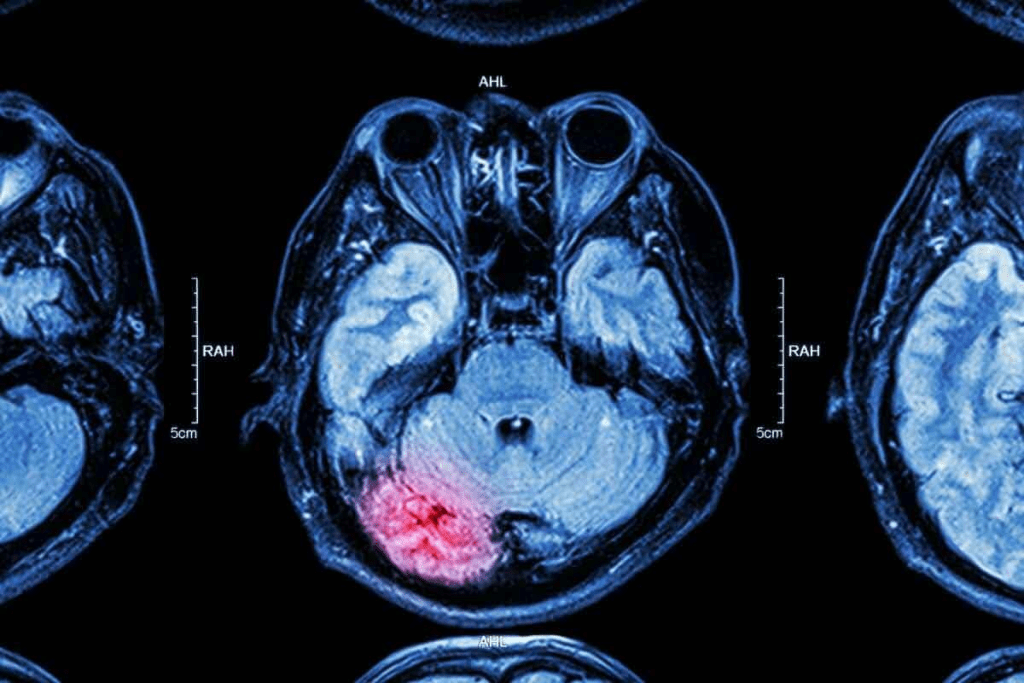

The Science Behind Brain Cancer Scans

Brain cancer scans use advanced imaging to find and show tumors. These techniques are key for spotting abnormal tissue and seeing how big tumors are.

How Medical Imaging Detects Abnormal Tissue

CT and MRI scans find abnormal tissue in different ways. CT scans use X-rays to make detailed brain images, showing where things are off. MRI uses magnetic fields and radio waves for clear images of soft tissues, helping spot brain tumors.

Experts say MRI is better than CT for finding some brain tumors, like small ones or those in hard-to-see spots.

Contrast agents make tumors easier to see during scans. These substances, like gadolinium for MRI or iodine for CT, are given to patients before scanning. They highlight abnormal tissue, helping doctors see tumors more clearly.

This clear view helps doctors make accurate diagnoses and plan treatments. Medical experts say contrast agents make imaging better, helping doctors see tumors more precisely.